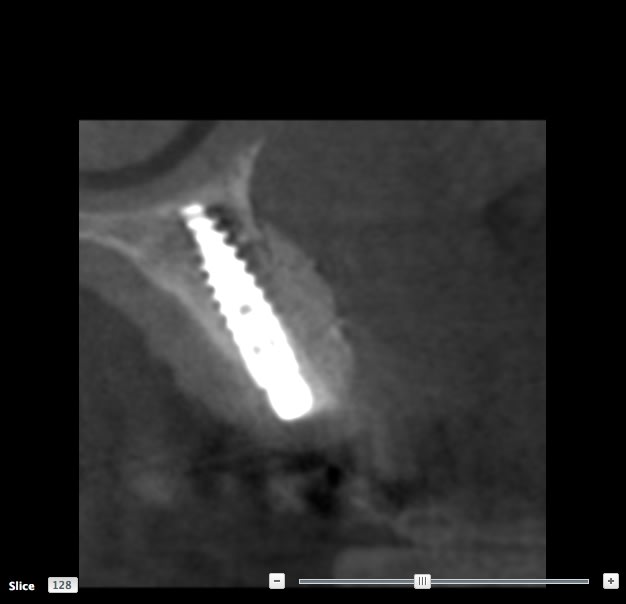

SCAN

Il y a 3.6 mm d'os au dessus du granulome